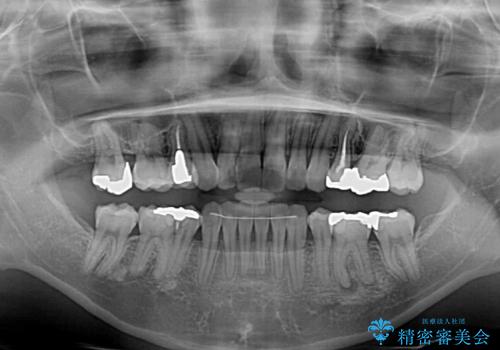

- 抜歯矯正の後戻りで前歯が突出してきていることを気にして来院された患者様です。

口元の突出感を改善するにあたり、抜歯矯正は行うことができないため、奥歯の後方移動とIPR(歯と歯の間を削る)により達成することとしました。

再度後戻りしたときに対応しやすいよう、インビザラインにて矯正治療を行うこととしました。

舌の突出癖がなかなか改善できず、IPRによる前歯の隙間が閉じきらずに、予定よりも長い治療期間となりました。